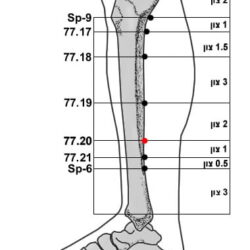

הסבר והדגמה של קריסטל המים 66.13 Shui jing

קריסטל המים 66.13 Shui jing היא נקודה חשובה באקופונקטורה של מאסטר טונג לטיפול בהפרעות גינקולוגיות, בוידאו אני מסביר אודות הנקודה ומדגים את בדרך לאתר ולדיקור.

הסבר והדגמה של קריסטל המים 66.13 Shui jing קרא עוד »